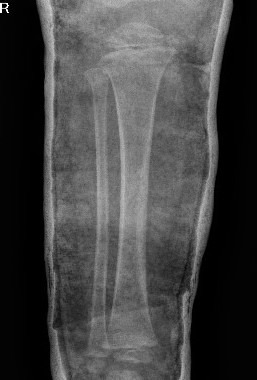

Valgus malalignment